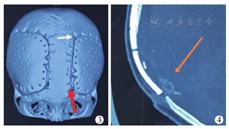

仿生骨瓣松动的原因较复杂,8例全部涉及额部,并且患儿均无脑软化或脑坏死(3例面积为50~100 cm2,5例面积>100 cm2)。可能是处在生长发育期的患儿,额叶的发育速度远大于其他脑叶的发育。一旦脑的膨胀速度快于仿生骨的"延展"速度及仿生骨-自体骨"键合"的速度,脑组织向外的膨胀力使得仿生骨材料四周与自体骨之间缝隙变宽,无法完成"键合"性骨连接[9]。并且在早期手术中,使用双10号线固定骨瓣,其线结本身的高张力对患儿自体骨形成"剪切作用"(图3),导致骨孔周围萎缩退化,线结固定相对"豁脱"[10]。之后均改为双7号丝线固定,线结松紧适度,位置远离切口。同时部分患儿术前脑压较高,脑积水未能解决,脑的搏动性压力传递也加剧了骨瓣松动。因此我们建议,对于有脑积水的患儿应先处理脑积水再行颅骨修补手术。脑膜脑膨出的患儿在修补术中应切除部分坏死的脑软化灶,必要时可做脑室造瘘,促进脑脊液回流。对于处于两个生长发育高峰、脑实质未受大损伤的患儿,术中需在额颞部相应部位加用PEEK颅骨锁固定。如在二次术中见仿生骨材料与自体骨之间已经出现较大缝隙,有结缔组织长入,估计骨"键合"困难者,须在清除结缔组织后(图4),在缝隙间填塞胶原骨泥(奥精医疗科技有限公司,中国),利用其强大的诱导能力促进骨健合。